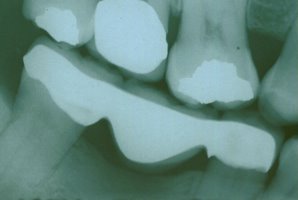

Orthodontics To Upright A Severely Tilted Molar

This patient had lost his first molar and the molar behind it collapsed

into the residual space. This was not a situation that was conducive to

placing a fixed bridge because of the misalignment. By performing a

simple, minor orthodontic procedure, the tooth was uprighted into its

original position and replaced with a beautiful fixed bridge. Now this

patient is able to chew his food properly, and lessen his chances of TMJ

(jaw joint) problems. |